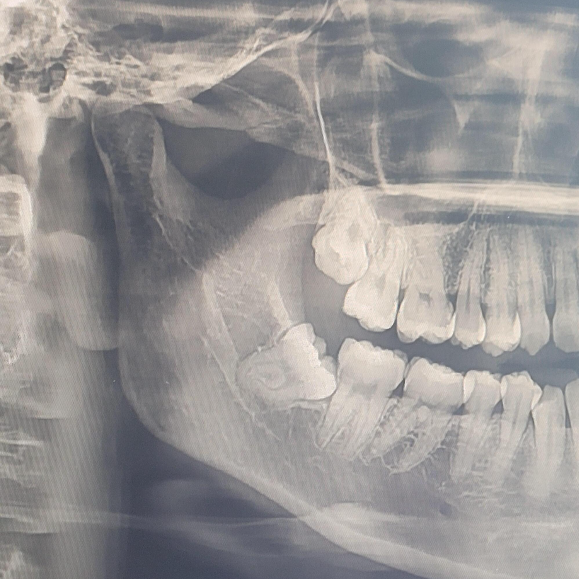

치과 멀리까지 가기 귀찮아서 집 근처에서 진료를 받아보고 있습니다. 2월에 X-ray 촬영 이후 여름에 인레이, 닳은 잇몸 치료까지 한 곳에서 했기 때문에 자료가 많이 남아있을거란 생각이 들어서 따로 병원을 옮기지는 않았습니다. 지난 2월 X-ray 촬영차트를 보더니 오른쪽 아래 매복 사랑니가 있다며. 사랑니가 밀어서 잇몸이 붓고 통증이 있는거라 하셨습니다.

몇년 전, 왼쪽 아래 사랑니를 뽑았을 땐 살짝 잇몸 밖으로 나와있어서 음식물도 많이 끼고, 또 비교적 바르게 자란 편이라 사랑니 뽑는 시간이 순삭이었습니다. 별로 아픔에 공감하지 못했는데, 오른쪽은 신경을 살짝 건드리고 가는 것 처럼 보여서 정확한 판단을 위해 CT촬영까지 했습니다.

CT결과는 다행히도 살짝 스치긴 하지만 이 정도는 신경손상을 걱정하지 않아도 되는 정도라고 하셔서 병원에서 무리없이 뽑을 수 있다고 하셨습니다. 월요일 오전에 매복사랑니 발치 예약을 해 두고 방문했습니다. 이제부터 생생후기입니다.